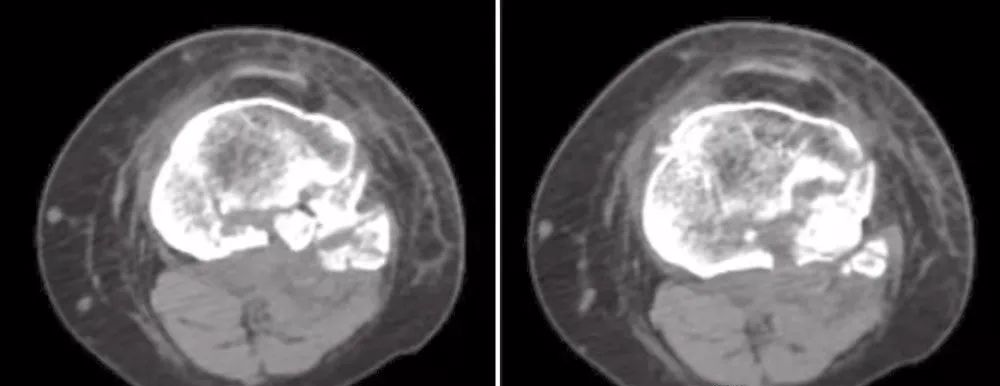

影像

图2 X线片,CT, MRI资料

X线片对于急诊诊断骨折很有帮助。然而,关节内的病理解剖用CT来划定更合适。冠状面上粉碎性骨折中关节内损伤、塌陷以及骨折解剖的程度在CT扫描上更为形象。如果怀疑有半月板和韧带损伤,可以用MRI进行评价(图2)。